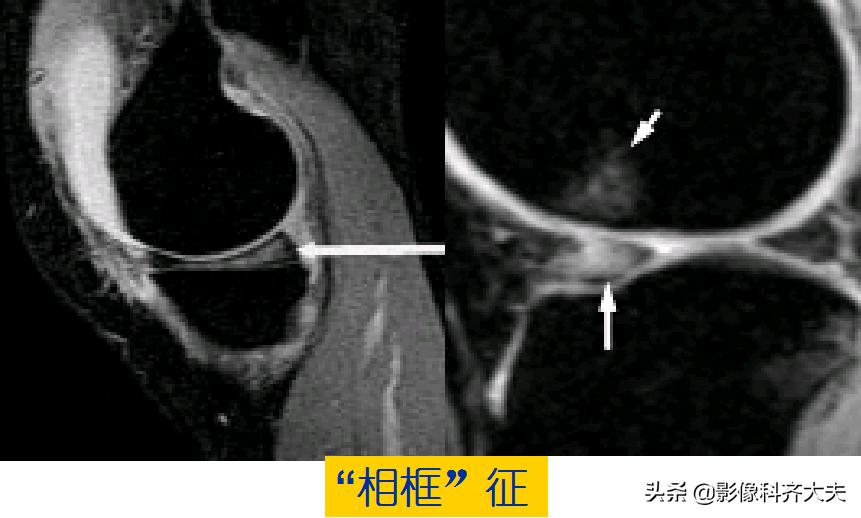

容易误诊为半月板损伤的正常解剖结构

膝横韧带:

腘肌腱腱鞘:

后股板韧带:

关节内气体伪影:

内侧半月板后角上隐窝: